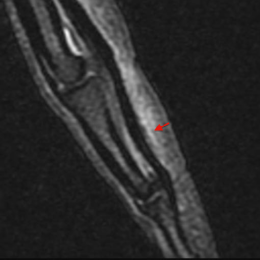

A : Coupe sagittaleT2  du 4e rayon digital : respect de la continuité et du signal des tendons fléchisseurs. Epaississement à la face profonde des fléchisseurs avec augmentation de la distance corticale antérieure - fléchisseurs. Epaississement du siège anatomique de la poulie A4.

Rupture de la poulie A4.